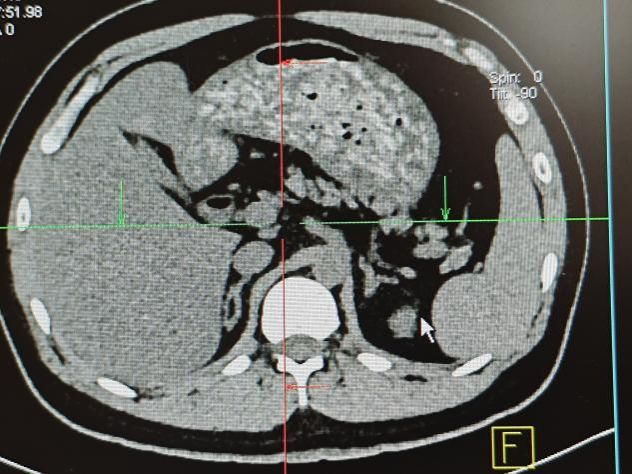

我的实习第一站是影像科,在这里我学会了“透过影像看本质”。罗老师教会我解读X光片、CT影像,详解不同疾病的影像特征,让我明白精准的影像诊断是康复治疗的重要前提。曾经以为影像科只是“看片子”,真正做时才发现这需要极强的细心耐心与专业积累,每一个细微的影像变化都可能影响治疗方案的调整。这段经历让我在后续的康复评估中,能更好地结合影像结果制定科学合理的治疗计划。